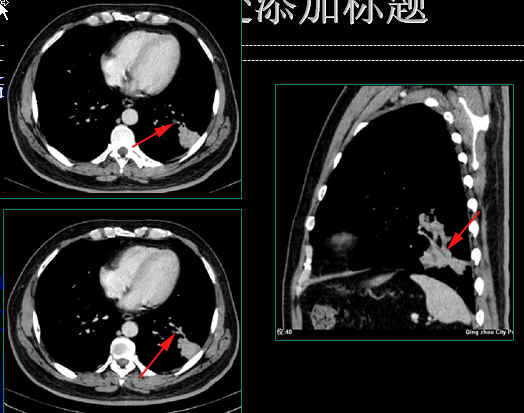

大体病理所见:左肺下叶外基底段实变,由远至近分多刀横切不张之肺实质,肺段内支气管扩张,扩张之支气管内显示大量脓性粘液溢出,基底干支气管远端见直径0.8cm的结节,向下延伸至外基底段支气管内,呈长条状结构,前内、后基底段支气管开口狭窄。

镜下所见:支气管内查见乳头状鳞状细胞增生,细胞异型,见较多核分裂像,肿瘤大部在支气管内游离,未侵犯支气管壁。

病理诊断:鳞状上皮乳头状癌。

下图箭头所指为阻塞后充满粘液的扩张支气管1